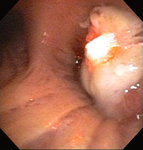

Бронхоскопическая терапия для обструкции нижних дыхательных путей правого главного бронха: постмеханическая циторедукция

Из коллекций Хосе Фернандо Сантакруза, дипломированного врача, члена Американской коллегии специалистов в области торакальной медицины, DAABIP, и Эрика Фолка, дипломированного врача, магистра наук; используется с разрешения